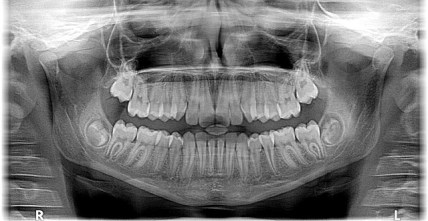

The dentist came into the room with a copy of my dental x-ray in his hand. He gave me a big smile, that actually made me more nervous than calm, and went out of his way to promote the benefits of the practice’s 360-degree panoramic x-ray machine. He explained how the x-ray shows all the teeth in both the upper and lower jaws on a single X-ray. He went onto say that they found the x-ray useful in identifying impacted teeth and aiding in diagnosing tumors.

I thought about everything, but what the dentist was saying. I would have continued to zone out, but he pointed to two circled portions of the x-ray and said, “everything looks good, except for these two portions of your jaw. They worry me.”

His stubby little finger highlighted several small pebble-like circles on both jaws. It hit me that I really should start paying attention. “What” I asked. He repeated what he had said and with only a couple of words, he had my full attention. I forgot about the time, my To Do List, and my morning coffee. I focused on everything the dentist was saying and wasn’t saying.

He explained that the fleshy circles were worrisome and he was going to send the x-ray to an oral surgeon for review. I pressed him for answers. “That’s great that you’re getting a second opinion, but what do you think?” I asked.

He hesitated and tried to push me off, stating that the oral surgeon would know better. I pressed again, asking if he had ever seen anything like it in his 30-year dental practice. He reminded me that the surgeon was the expert in reading the x-ray, but he said he was worried about kidney stones or worse a blockage in the carotid artery. He vaguely referenced something about cancer too.

Fortunately, the doctor had good news. I let out a little yelp when he told me that the nodules were simple tonsil stones, also known as tonsilliths, which are benign accumulations in the crypts of some people’s tonsils. They can sometimes cause minor discomfort, but generally are not dangerous.